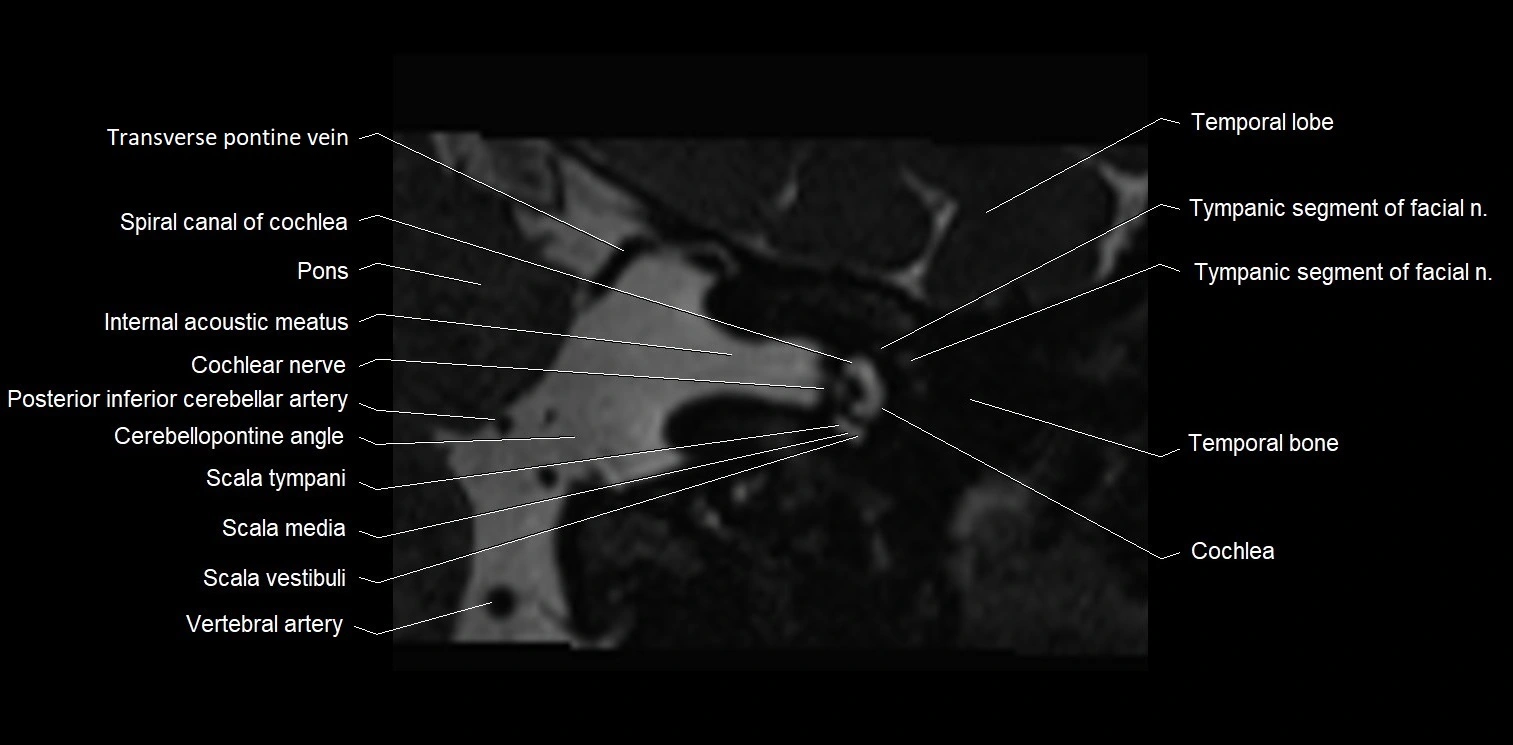

MRI Appearance

• The abducens nerve is a small, thin, linear structure

• Best visualized on high-resolution T2-weighted 3D MRI sequences (e.g., FIESTA or CISS)

• Seen as a hypointense (dark) line running from the brainstem at the pontomedullary junction, traversing the prepontine cistern, and entering Dorello’s canal under the petrosphenoidal ligament, then into the cavernous sinus, and finally the orbit

• May be challenging to visualize in standard MRI due to its small size

• Pathology may be inferred by absence, displacement, or enhancement of the nerve